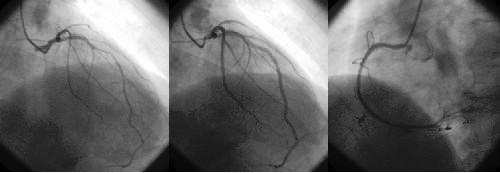

后來做冠狀動脈造影,一注射造影劑就看到左側(cè)的冠狀動脈都比較細(xì),病人感輕度胸悶不適,醫(yī)生向冠脈內(nèi)注入硝酸甘油200μg后左冠狀動脈各血管都顯影良好,右冠及主要分支也沒見到狹窄(下圖)。

左圖:左冠狀動脈痙攣 中圖:注射硝酸甘油后 右圖:右冠狀動脈